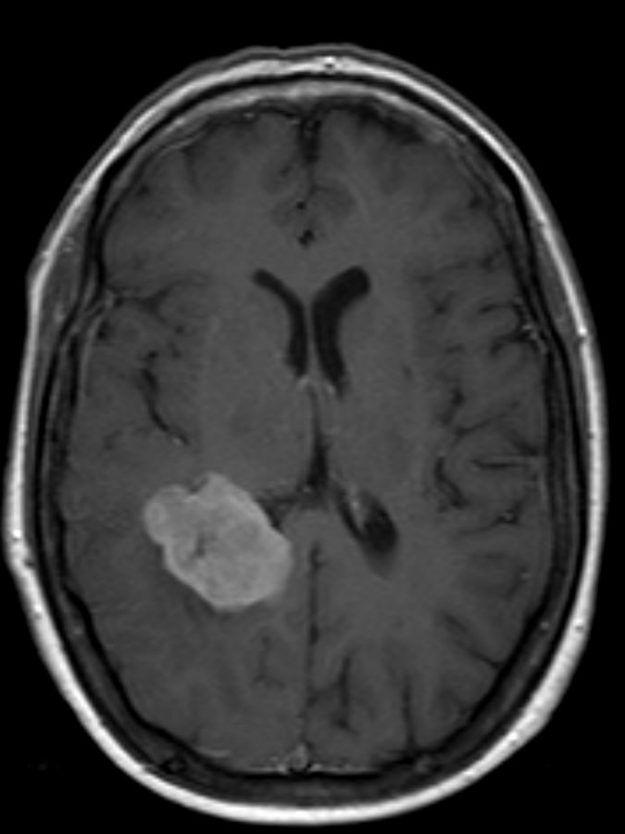

Μηνιγγίωμα περιοχής Επίφυσης

Ασθενής γυναίκα, 52 ετών η οποία παρουσίασε υπακουσία και επεισόδια πάρεσης του προσώπου. Ο απεικονιστικός έλεγχος με μαγνητική τομογραφία ανέδειξε ευμεγέθη όγκο στην περιοχή της επίφυσης (κωνάριο) με πίεση επί του μεσολοβίου, του τετραδύμου πετάλου και λοιπών εν’ τω βάθει δομών. Διενεργήθη δεξιά ινιακή, διασκηνιδιακή, διαδρεπανική προσπέλαση και ολική αφαίρεση της βλάβης. Η μετεγχειρητική αξονική…